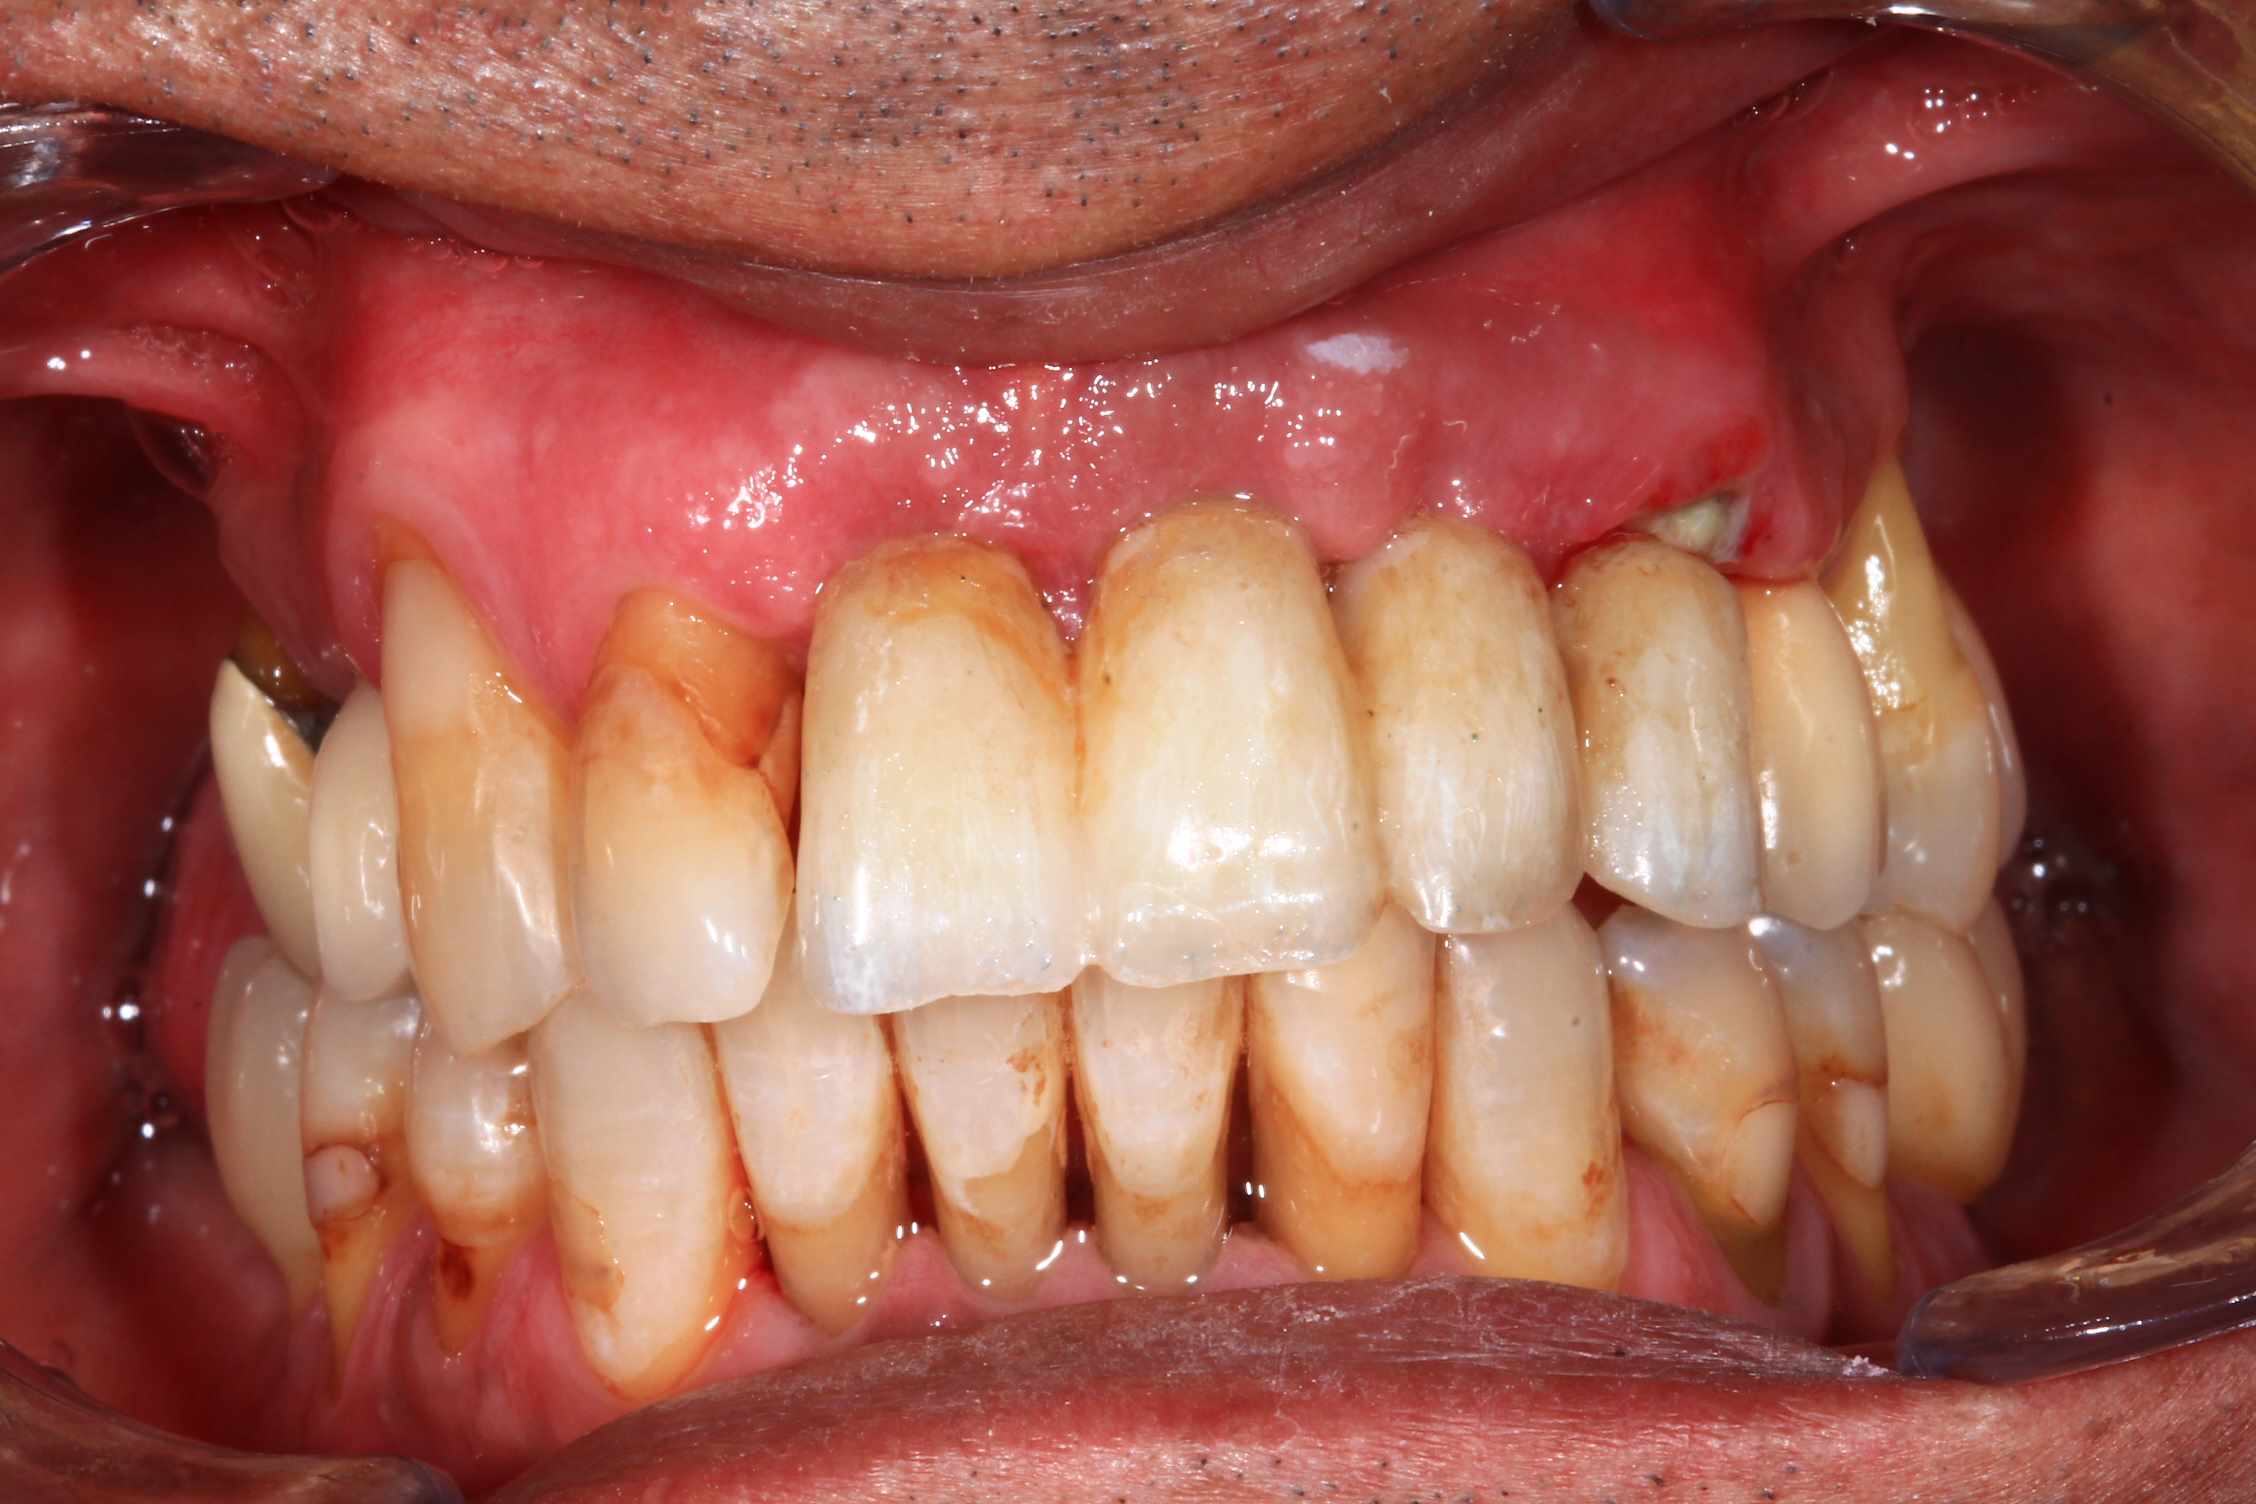

Mais celui la est tout chaud ( de vendredi dernier ) et j'ai regarder le temps que j'ai mis ( beaucoup plus complexe, donc plus long ). on va l'appeller Cas 2.

3 h de planif, modélisation du guide, puis 2 h environ pour la simulation de la chir , le modelisation et l'impression du bridge, qui tombe pile, zero retouche occlusale.

Avec un plan de traitement qui est suceptible de débat :)

Cas 2 , suite : avec une saussage au passage..

le patient arrive a 9 h, Prise de sang, PRF, injection de corticoïde, anesthésie et installation au bloc. Premier coup de bistouri a 9h30. Dernière suture a 11h30.